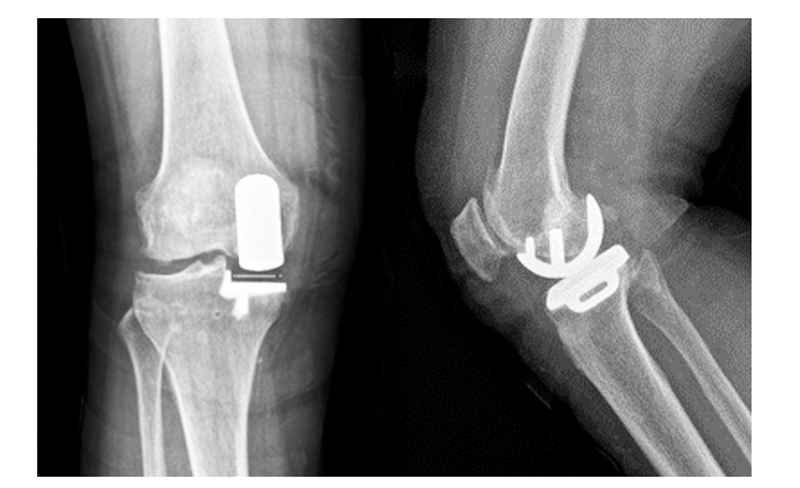

(2)65岁女性患者,以右膝关节疼痛3年、加重半年为主诉入院,入院查体右下肢内翻畸形8°,膝关节内侧间隙压痛阳性,外侧无压痛,浮髌试验阴性,髌骨研磨试验 阴 性,抽 屉 试 验 阴 性,ROM10°~130°,诊断为右膝关节前内侧骨关节炎,行 Oxford活 动 平 台 内 侧 单髁置换术。术后24h内间断 冰 敷,给予预 防 感 染、消 肿 止 痛及抗凝 治 疗,术 后24h康复师指导助行器辅助下床活动,术后1个月膝关 节 HSS评 分 由62分升至81分,KSS评 分 由50分升至85分,内侧疼痛消失,手术效果良好。手术前后影像学资料见图3~4。

图4术后 X线片示假体位置良好,大小合适,活动垫片在位